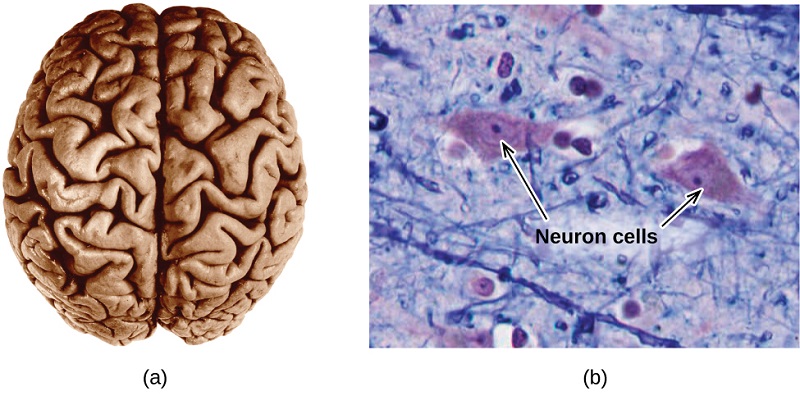

The brain is the control center of the central nervous system (see image below). It sends and receives signals to and from muscles and other internal organs to monitor and control their functions; it processes stimuli detected by sensory organs to guide interactions with the external world; and it houses the complex physiological processes that give rise to our intellect and emotions.

(a) A typical human brain weighs about 1.5 kg and occupies a volume of roughly 1.1 L. (b) Information is transmitted in brain tissue and throughout the central nervous system by specialized cells called neurons (micrograph shows cells at 1600× magnification). Image credit: OpenStax, Chemistry